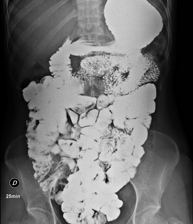

Prova diagnòstica que consisteix en obtenir imatges radiològiques en moviment de l'esòfag, estómac i duodè mitjançant l'ús de raigs X (fluoroscòpia) i d'un contrast opac baritat que s'administra per via oral. - Trànsit intestinal

Prova diagnòstica que consisteix en obtenir imatges radiològiques en moviment de l'esòfag, estómac, duodè i intestí prim mitjançant l'ús de raigs X (fluoroscòpia) i d'un contrast opac baritat que s'administra per via oral. - Ènema opac doble contrast

Prova diagnòstica que consisteix en obtenir imatges radiològiques de l'intestí gros (còlon i recte) mitjançant l'ús de raigs X. S'utilitza un contrast opac que s'administra a través del recte en forma d'ènema i també s'introdueix aire per expandir el còlon.